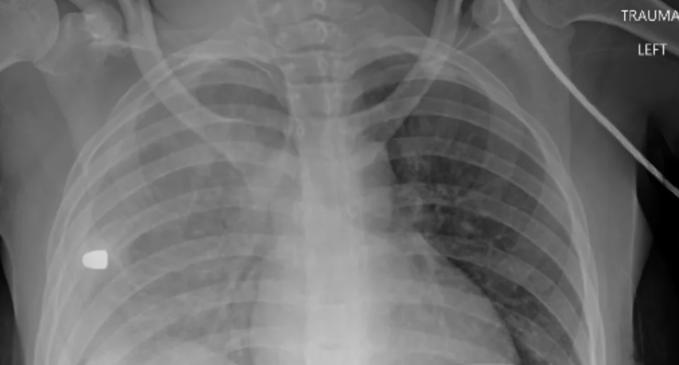

Ảnh X-quang tiết lộ nguyên nhân khiến nhiều trẻ em Mỹ tử vong. Ảnh chụp X-quang được một bác sĩ chia sẻ cho thấy các sự cố liên quan súng đạn là nguyên nhân gây tử vong hàng đầu cho trẻ em Mỹ.

Hôm 28/3, bác sĩ Sam Ghali, làm việc tại khoa Cấp cứu, Trung tâm Y tế Đại học Toledo, đã đăng bức ảnh chụp X-quang lồng ngực của một thiếu niên lên Twitter, cho thấy phổi của bệnh nhân dường như có dị vật. Ông đề nghị mọi người đoán nguyên nhân.

"Đây là phim chụp X-quang lồng ngực của một thiếu niên đang phải gánh chịu một tình trạng - hiện là nguyên nhân gây tử vong số một ở trẻ em và thanh thiếu niên Mỹ. Bạn hãy thử chẩn đoán xem?", ông đặt câu hỏi.

Sau đó, vị bác sĩ tiết lộ dị vật trong phim chụp X-quang này là một viên đạn, găm vào lồng ngực thiếu niên sau sự cố liên quan súng đạn. Danh tính nạn nhân không được tiết lộ. Theo bác sĩ Ghali, đây cũng là nguyên nhân số một khiến nhiều trẻ em Mỹ qua đời trong thời gian qua.

Mảnh đạn trong ngực trái của một bé gái tại Mỹ. Ảnh: Sam Ghali